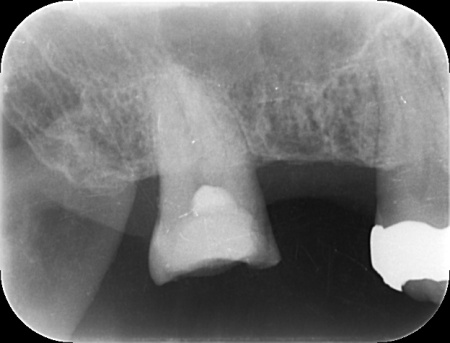

虫歯をしっかりと除去したところ、一部で神経の露出が確認されたためMTAセメントを用いて神経を保護し、上から密閉性の高い材料で覆っています。

その後、仮の被せ物を装着して経過を観察しました。

数週間後、しみたり痛んだりする症状は認められず、コールドテストとバイタルテストでも歯の神経が問題なく機能している状態であると判断できました。